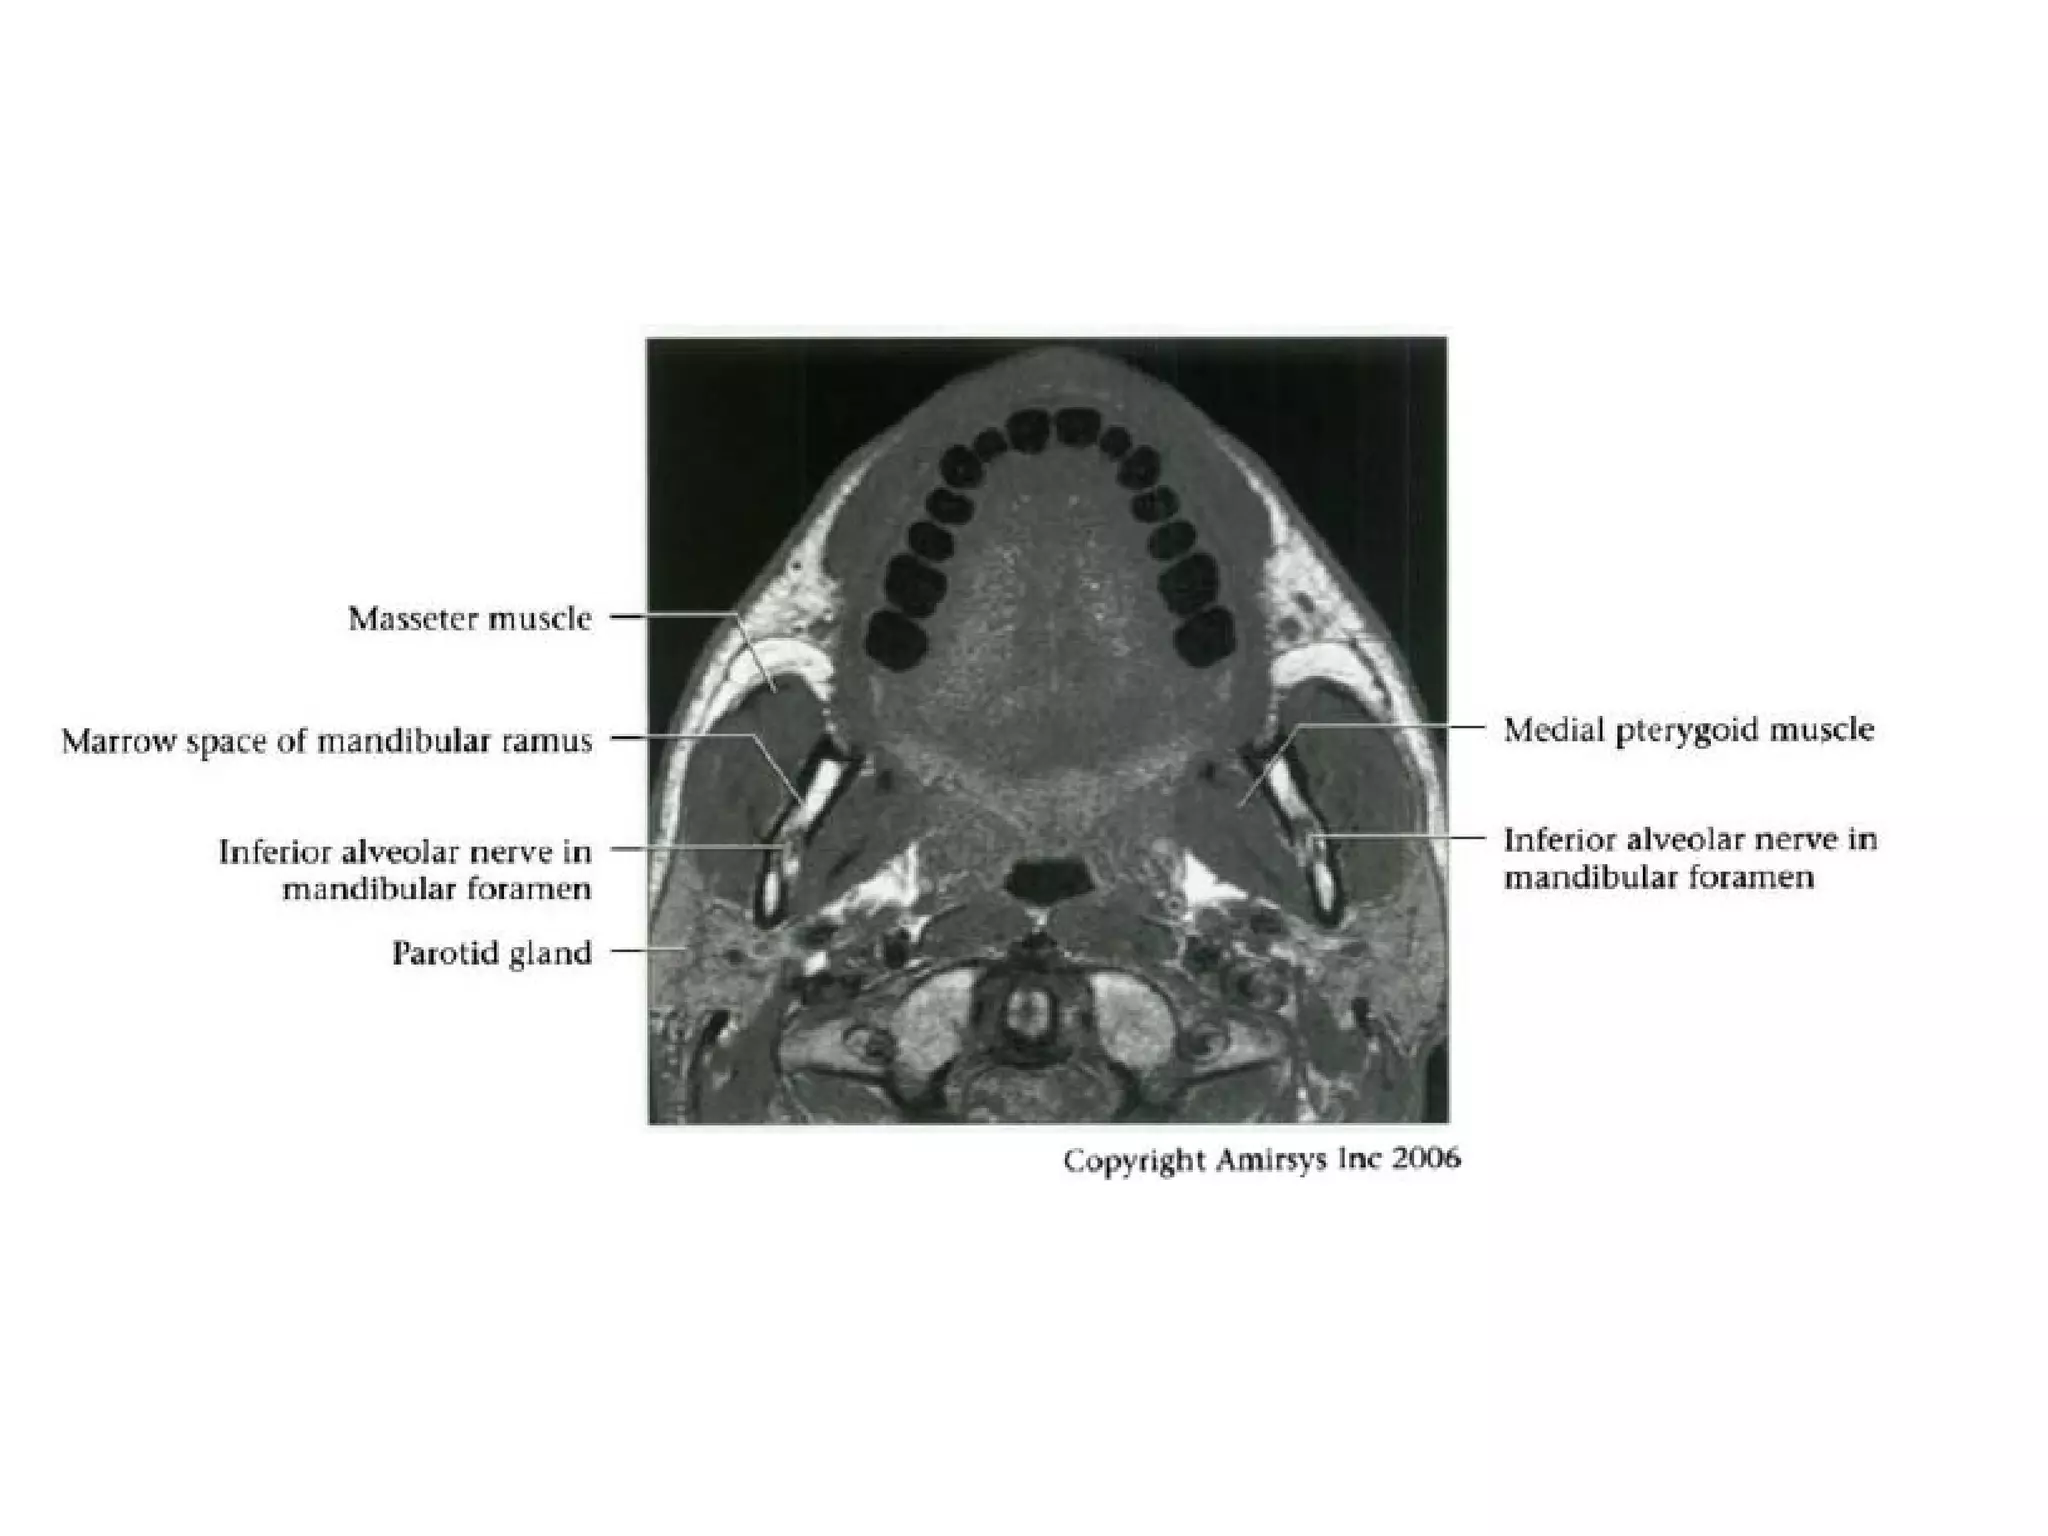

Divisions (Post-Ganglionic) of CNS

Mandibular nerve (CNV3)

• Does not pass through cavernous sinus

• Exits directly from Meckel cave, passing inferiorly

through foramen ovaIe into masticator space

• Carries both motor and sensory fibers

- Motor root bypasses TG, joins V3 as it exits through

foramen ovale

- Divides into masticator (muscles of mastication) and

mylohyoid nerves (mylohyoid and anterior belly of

digastric muscles)

- Masticator nerve take off just below skull base

- Mylohyoid nerve take off at mandibular foramen

• Main sensory branches include inferior alveolar, lingual

and auriculotemporal nerves